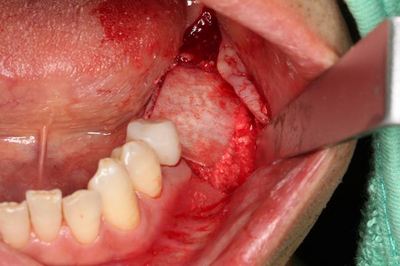

この段階で粘膜剥離して実際の骨の状態を確認します。

この部分は歯根破折と炎症のある歯を抜歯していますので

軟組織が存在し完全な骨性の治癒ではありません。

ドリリングを進め、軟組織を除去しました。

骨欠損部分には骨補填材を填入しますが、まずは埋入を行います。